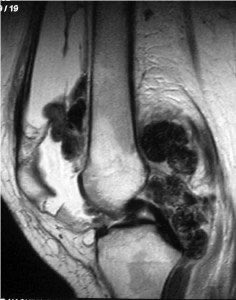

BREAKING: Utah Jazz star Jaren Jackson Jr. is likely to miss the remainder of the season to undergo surgery on his left knee to ensure his longterm health after a localized PVNS growth was discovered post trade, league sources tell me.